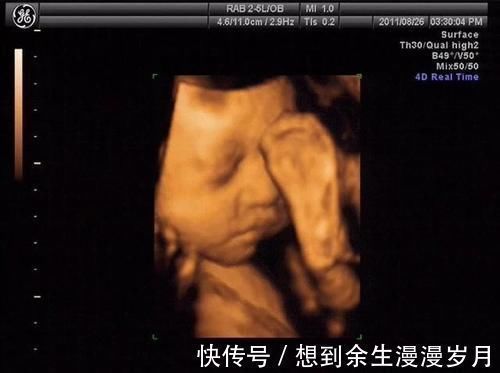

一.彩超看胎儿的原理是什么?我们通常看胎儿使用二维彩超就可以了,这种彩超技术看胎儿的原理就是把所见到的影像形成一个切面,呈现出一个平面展现出来,非常直观,胎儿主要看胎儿的四肢和身体结构使用二维彩超即可以看见。现在的二维彩超在平面技术的基础上加上了血流信号的显示,就是我们经常去做的多普勒超声检查,在妇产科主要看胎儿脐血流,心脏血流情况,通过血流信号可以判断胎儿血流供应情况。

【 面部|做四维医生说腹部脂肪厚,看不清,打出来单子也只能看宝宝大概面部怎么办?】二.肚皮太厚,胎儿看不清怎么办?肚皮的厚度就像墙壁一样,超声的原理就是声波的穿透性,如果肚皮越厚,也声波越难以通过,在彩超机器上就难以显示出来。如果你看的是羊水量,脐血流其实影响不大,因为血流信号一般都能显示出来;如果看的是胎儿身体结构,则肚皮厚度超过5cm以上的孕妇则很难看清。此时磁共振是解决肚皮厚照不到胎儿的有效解决办法。